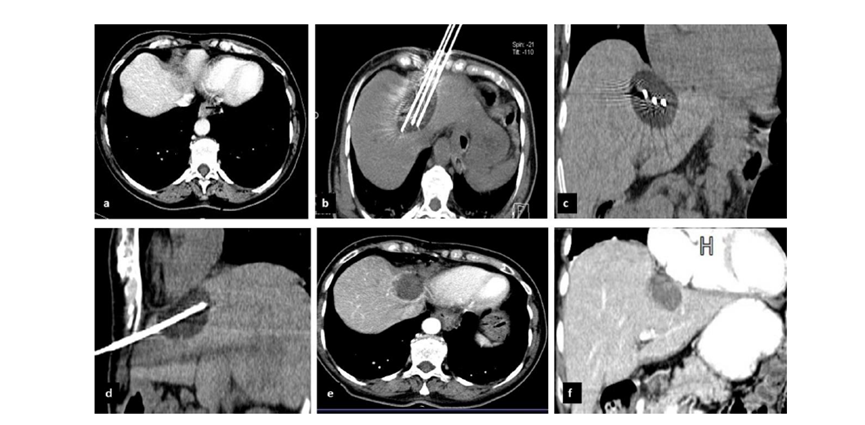

79 歲男性,肝轉(zhuǎn)移(結(jié)直腸癌)腫瘤的完全消融病例

( a ) 軸向 MRI 和 ( b ) 軸向 CT 顯示肝S8段有一個(gè)16mm的病灶,鄰近肝緣。( c )冷凍消融期間CT顯示放置了2個(gè)冷凍探針,低密度冰球包圍病灶。(d)術(shù)后1個(gè)月隨訪 CT顯示冰球?qū)?yīng)的壞死區(qū)域,未見復(fù)發(fā)。(e)術(shù)后6個(gè)月的CT,壞死區(qū)域縮小,未見復(fù)發(fā)。(f)與基線影像(g)相比,12個(gè)月后的FDG-PET/CT顯示未見FDG攝取。

62歲女性,肝轉(zhuǎn)移(卵巢癌)腫瘤的完全消融病例(a)軸向CT顯示病變位置毗鄰心臟和上腔靜脈(黑色箭頭)。(b)術(shù)中軸向CT掃描:使用三個(gè)冷凍探針。1個(gè)月后的軸向(e)和冠狀位(f)增強(qiáng)CT掃描顯示低密度區(qū)域,由于肉芽組織反應(yīng)引起的邊緣增強(qiáng)。

技術(shù)成功100%,92% 的病灶中觀察到腫瘤完全消融。16 名患者 (33%) 出現(xiàn)局部復(fù)發(fā)。10 名患者 (20%) 因局部復(fù)發(fā)或腫瘤消融不完全而接受二次冷凍消融術(shù)。

7名患者出現(xiàn)輕微并發(fā)癥,未發(fā)現(xiàn)膿腫形成、膽漏、膽汁瘤或血液學(xué)變化。冷凍消融可安全、有效治療毗鄰重要臟器的原發(fā)性肝臟腫瘤和肝轉(zhuǎn)移瘤患者,有效控制腫瘤局部進(jìn)展,使患者生存獲益。我國(guó)作為肝癌大國(guó),對(duì)于肝癌的治療一直給予高度重視?;趯<夜沧R(shí)和相關(guān)文獻(xiàn)研究結(jié)果顯示,冷凍消融技術(shù)具有高效、低成本、創(chuàng)傷小、適應(yīng)證廣、并發(fā)癥相對(duì)較少等優(yōu)點(diǎn),可有效延長(zhǎng)患者生存期、提高生活質(zhì)量、降低患者經(jīng)濟(jì)負(fù)擔(dān)。因此,冷凍消融技術(shù)在肝癌的應(yīng)用中有著極高的潛力和廣泛的發(fā)展空間。